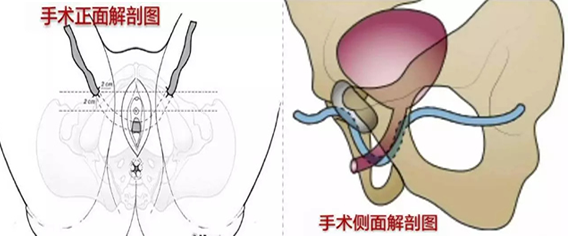

四川现代医院泌尿外科治疗女性压力性尿失禁是采用TVTO吊带微创治疗。TVTO吊带微创手术是目前最新、也是最肯定的治疗压力性尿失禁的手术方法,以人工网袋置于中段尿道,加强耻骨尿道韧带(PUL)。当腹部用力、腹压增加时,PUL被当成支点,让骨盆底肌肉群协同作用,托住中段尿道保持不漏尿状态。TVTO手术,操作时间短,无明显的手术瘢痕,具有微创及并发症少等优点,深受患者欢迎。

6、TVTO吊带微创治疗女性压力性尿失禁